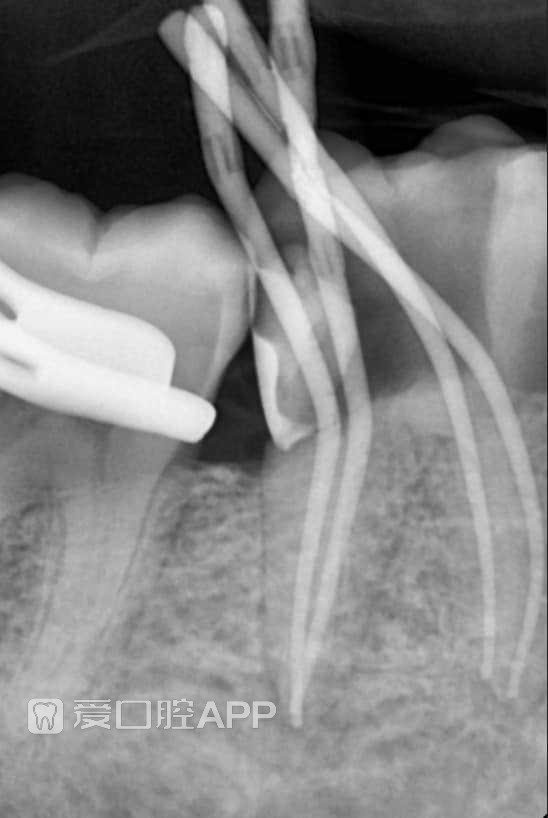

看个根充 —— 下6

by Mohamed Abdul-Aziz